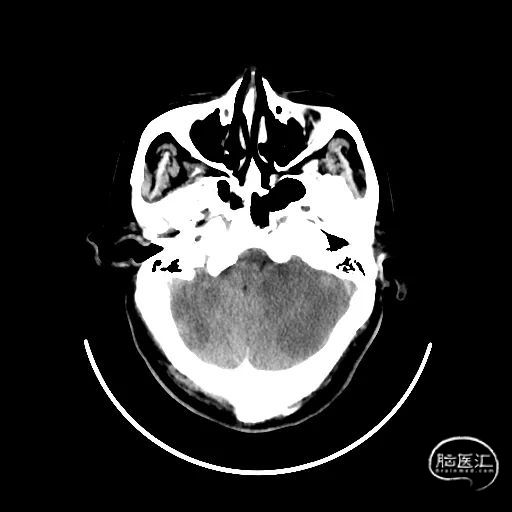

术后CT:未见明显脑出血,双侧小脑低密度影。

术后9天MRI:

术后第一天:神志清楚,言语正常,头晕,共济失调,双侧瞳孔等大正圆,直径3mm,对光反射灵敏,四肢肌力5级,NIHSS评分1分。

术后第九天:恢复出院。